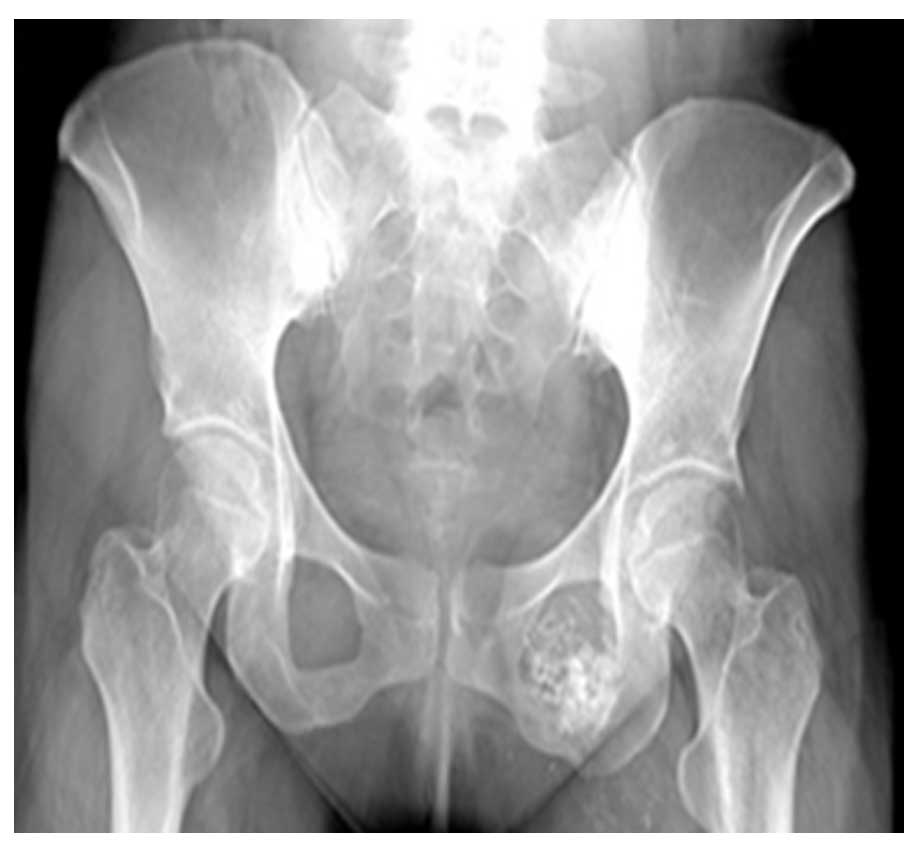

Ameliyat Öncesi: Röntgende sol pubik kolda düzensizlik ve sklerotik tümör dokusu görülmekte.